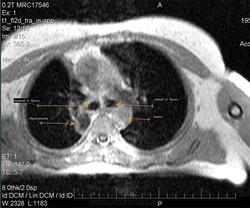

Случай 1. Пациент А. Женщина 52 года, после оперативного лечения (верхняя лобэктомия справа) 26.03.2009г. Гистологическое заключение: железисто-солидный вариант (низкодифференцированная аденокарцинома) с метастазами в бронхопульмональные лимфоузлы. Проведен послеоперационный курс дистанционной гамма-терапии, при контрольном ультразвуковом исследовании органов брюшной полости выявлено метастатическое поражение печени. Диагноз: немелкоклеточный рак правого легкого 4й стадии. На МР-томограммах определяются образования области верхушки правого легкого, корня правого легкого, печени. На КТ-томограммах определяются образования области верхушки правого легкого, утолщение плавры (исследование проведено через 7 месяцев после МРТ).

Вокруг правого главного бронха муфтообразное утолщение, кзади участок пневмонита, обтурация сегментаного бронха.